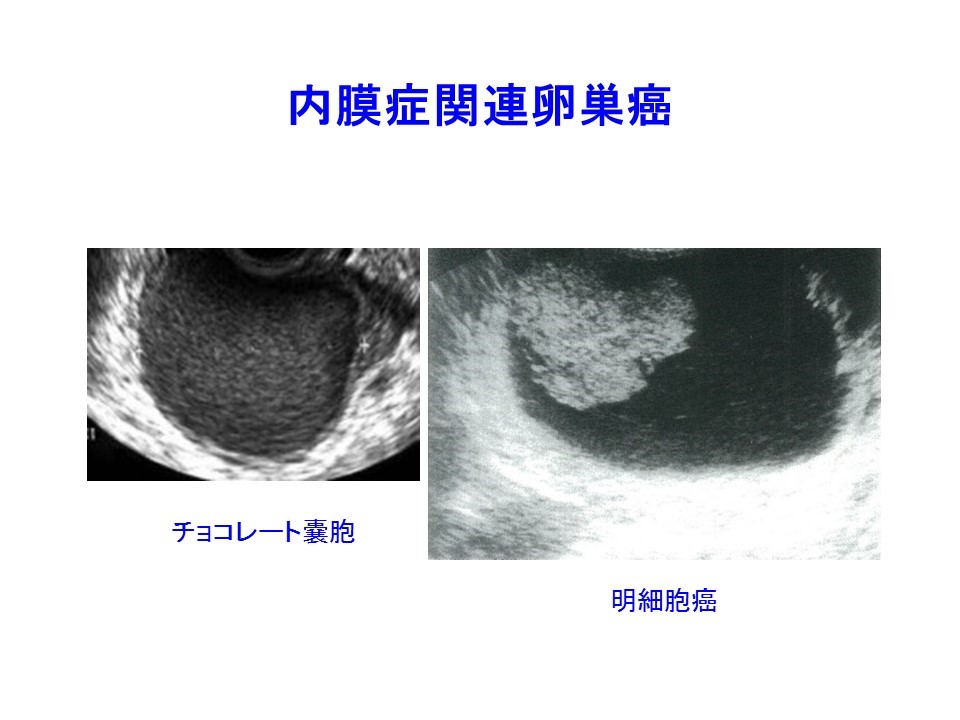

3. チョコレート嚢胞患者を高次医療機関へ紹介するタイミング:サイズ・エコー輝度・隆起性病変 日本産婦人科医会

6. チョコレート嚢胞に隆起性病変を認めたときに、癌・非癌を区別するにはどうすればいいのか? 日本産婦人科医会

生理痛がひどい。卵巣嚢腫。チョコレート嚢胞のエコー像。子宮内膜症。 らぴゅたった

3. チョコレート嚢胞患者を高次医療機関へ紹介するタイミング:サイズ・エコー輝度・隆起性病変 日本産婦人科医会